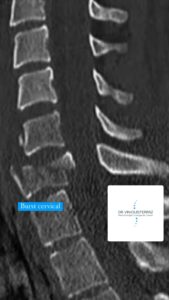

Diversos sistemas para classificar as fraturas cervicais subaxiais foram desenvolvidos ao redor do mundo, atualmente a maioria dos hospitais, centros de referência e profissionais da saúde que tratam pacientes com esse tipo de fratura utilizam a classificação elaborada pela AO Foundation (sigla do alemão para “Arbeitsgemeinschaft für Osteosynthesefragen”). A tomografia computadorizada (TC) é obrigatória para a classificação completa de uma lesão da coluna cervical, e raios X em flexo-extensão ou ressonância magnética (RM) também podem ser necessários para identificar possíveis lesões discais e ligamentares. Vale ressaltar que achados intraoperatórios podem modificar a classificação inicial.